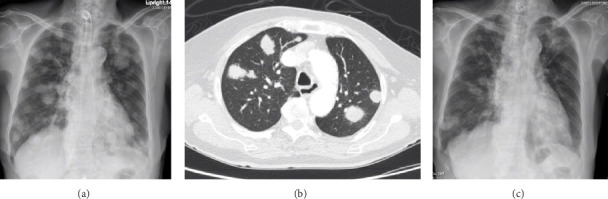

简介:甲状腺纤维肉瘤是一种非常罕见的肿瘤,文献报道的病例非常少。它们与间变性甲状腺癌的相似性给诊断带来了挑战,经常导致误诊。病例报告:我们报告一位87岁的女性,她有左侧甲状腺结节的病史,她接受了左侧肺叶切除术,随后接受了左甲状腺素治疗。她表现为右侧甲状腺有一个快速增长的肿块。她的甲状腺功能正常。超声显示右侧甲状腺上有一模糊的低回声肿块,大小为4厘米。行细针穿刺活检(FNAB),细胞学提示Bethesda VI为间变性甲状腺癌。甲状腺全切除术后,手术病理检查显示一个高级别纤维肉瘤,并延伸到带肌。注意到淋巴血管和神经周围浸润。免疫组化染色显示平滑肌肌动蛋白(SMA)阳性,配对盒基因8 (PAX8)、转录因子1 (TTF-1)、甲状腺球蛋白和上皮标志物(AE1/AE3)阴性。手术后,使用异环磷酰胺进行辅助放疗和化疗。然而,疾病进展并伴有肺转移。治疗改为帕唑帕尼,导致肺转移显著改善。然而,病情持续发展,患者在开始治疗后2年内死亡。结论:虽然甲状腺纤维肉瘤极为罕见,但在鉴别诊断间变性甲状腺癌时应予以考虑。免疫组织化学(IHC)在支持诊断中起着至关重要的作用。多学科方法对其管理至关重要。除手术外,新出现的激酶抑制剂辅助疗法已显示出改善患者生存的希望。

Introduction: Thyroid gland fibrosarcomas are very rare tumors, with only very few cases have been reported in the literature. Their similarity to anaplastic thyroid cancer poses a diagnostic challenge, often leading to misdiagnosis. Case Report: We report the case of an 87-year-old female with a history of left thyroid nodule who underwent a left lobectomy and subsequently, received levothyroxine therapy. She presented with a rapidly growing mass on the right thyroid gland. Her thyroid function was normal. Ultrasound revealed an ill-defined hypoechoic mass measuring 4 cm on the right thyroid. Fine-needle aspiration biopsy (FNAB) was performed, and cytology indicated Bethesda VI for anaplastic thyroid carcinoma. After the total thyroidectomy, the surgical pathological examination revealed a high-grade fibrosarcoma with extension into the strap muscle. Lymphovascular and perineural invasion was noted. Immunohistochemical staining showed positivity for smooth muscle actin (SMA), and negative for paired-box gene 8 (PAX8), transcription factor 1 (TTF-1), thyroglobulin, and epithelium markers (AE1/AE3). Following surgery, adjuvant therapy with radiation and chemotherapy using ifosfamide was administered. However, the disease progressed with lung metastasis. The treatment was changed to administration of pazopanib, resulting in dramatic improvement of lung metastasis. However, the disease continued to progress, and patient passed away within 2 years after treatment initiation. Conclusions: Although fibrosarcoma of the thyroid gland is exceedingly rare, it should be considered in the differential diagnosis of anaplastic thyroid carcinoma. Immunohistochemistry (IHC) plays a crucial role in supporting the diagnosis. A multidisciplinary approach is essential for its management. In addition to surgery, emerging adjuvant therapies with kinase inhibitors have shown promise in improving patient survival.